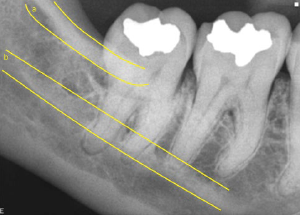

70. What is showing by arrow?

Alveolar bone Normally the level of the alveolar bone is 1.5-2mm apical to the CEJ of the adjacent teeth. In the anterior region the crest is sharp and pointed between the incisors. Posteriorly it is flat, aligned parallel with and slightly below a line connecting the CEls of the adjacent teeth.